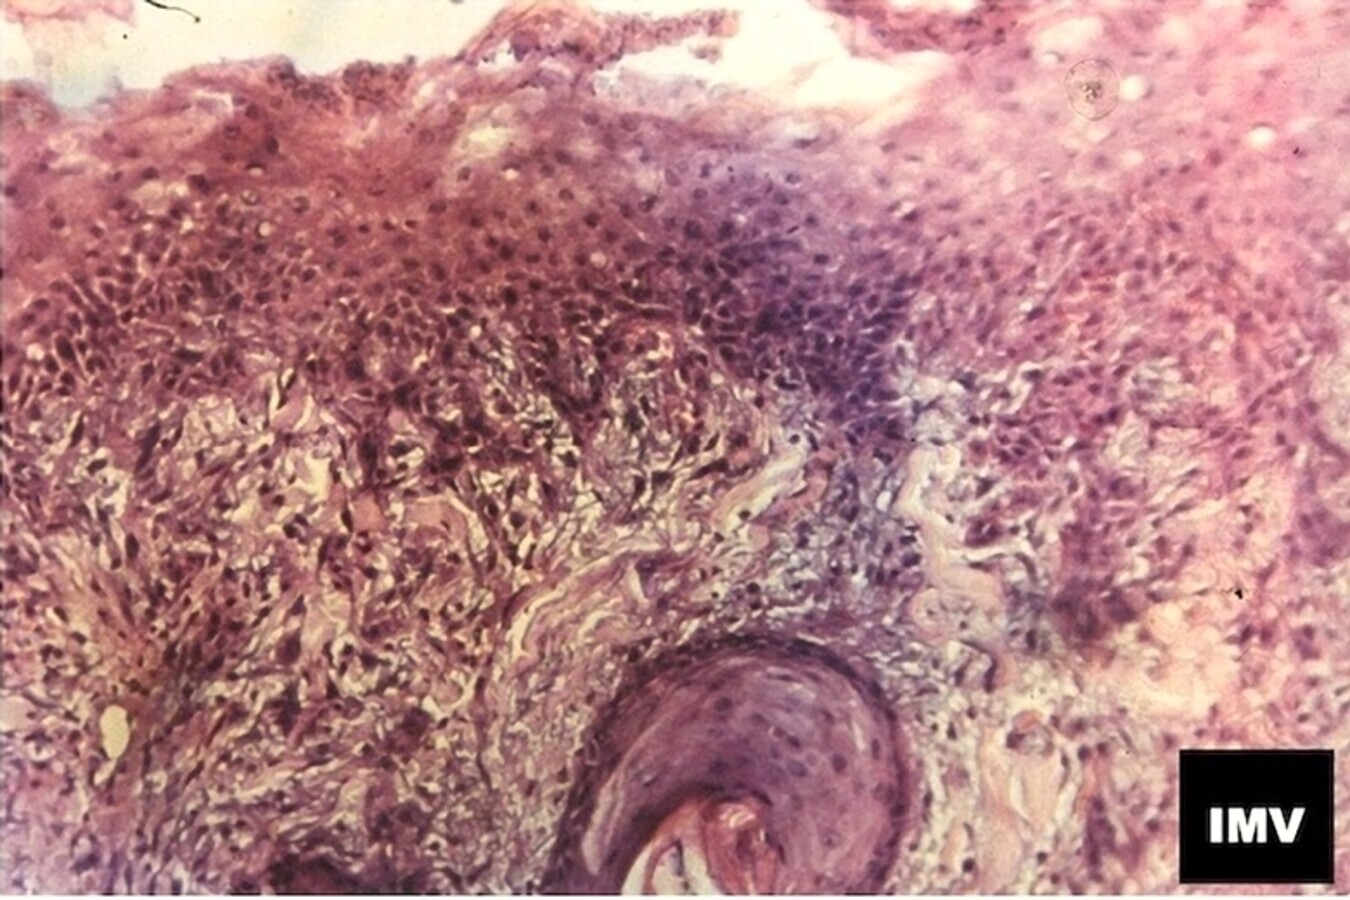

Figura 3. Muestra de piel x400 HE/EO, cinco días después del tratamiento de resurfacing con alta energía programada en el láser de CO2, para emisión en modo fraccional y con notable densidad de pulsos en el diseño seleccionado para el tratamiento. Se aprecian restos de dermis superficial con signos de coagulación y la imagen de un folículo piloso en la dermis profunda que “inyecta” activamente células con misión reparativa de la piel, una vez transcurrida la fase primera (inflamatoria) de reparación de una herida.